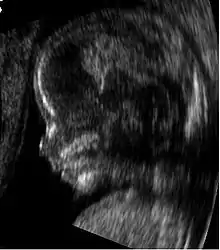

Medical ultrasound is an ultrasound-based diagnostic medical imaging technique used to visualize muscles, tendons, and many internal organs to capture their size, structure and any pathological lesions with real time tomographic images. Ultrasound has been used by radiologists and sonographers to image the human body for at least 50 years and has become a widely used diagnostic tool. The technology is relatively inexpensive and portable, especially when compared with other techniques, such as magnetic resonance imaging (MRI) and computed tomography (CT). Ultrasound is also used to visualize fetuses during routine and emergency prenatal care. Such diagnostic applications used during pregnancy are referred to as obstetric sonography. As currently applied in the medical field, properly performed ultrasound poses no known risks to the patient.[29] Sonography does not use ionizing radiation, and the power levels used for imaging are too low to cause adverse heating or pressure effects in tissue.[30][31] Although the long-term effects due to ultrasound exposure at diagnostic intensity are still unknown,[32] currently most doctors feel that the benefits to patients outweigh the risks.[33] The ALARA (As Low As Reasonably Achievable) principle has been advocated for an ultrasound examination – that is, keeping the scanning time and power settings as low as possible but consistent with diagnostic imaging – and that by that principle nonmedical uses, which by definition are not necessary, are actively discouraged.[34]

According to RadiologyInfo,[36] ultrasounds are useful in the detection of pelvic abnormalities and can involve techniques known as abdominal (transabdominal) ultrasound, vaginal (transvaginal or endovaginal) ultrasound in women, and also rectal (transrectal) ultrasound in men.